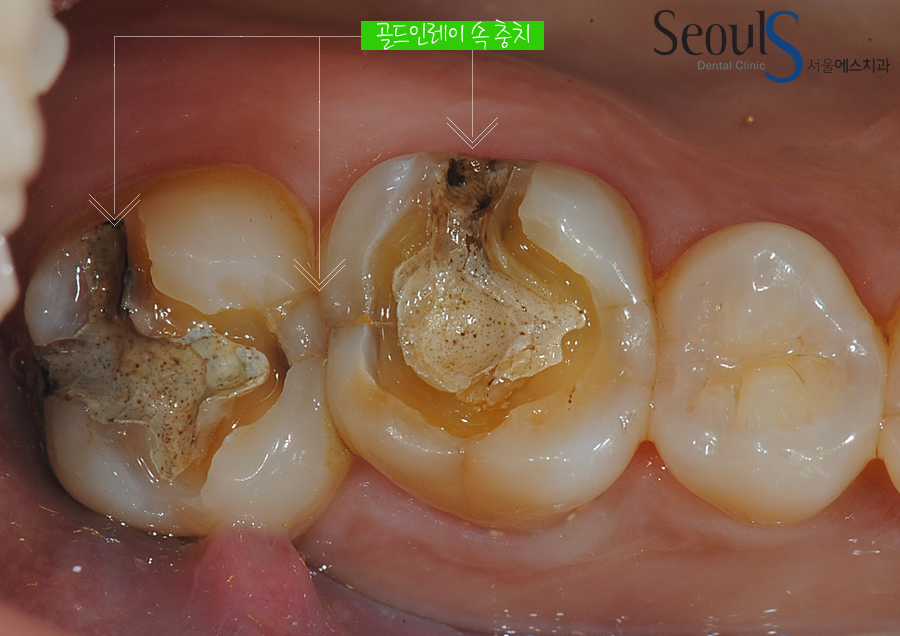

충치치료 후 금으로 때웠던 치아모습입니다

골드인레이 속으로 충치가 진행되고 있습니다

골드인레이를 제거했습니다

충치가 진행되고 있습니다 화살표로 표시한 부분에 충치가 진행되고 있고

사이 충치도 진행되고 있는 모습입니다